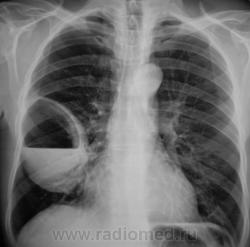

Лаборант «с флюорографа» пригласил посмотреть произведенную флюорограмму.

Лаборант «с флюорографа» пригласил посмотреть произведенную флюорограмму.роизвели рентген

Произвели рентгенографию в стандартных проекциях.

Флюорограмма 2009 года.

сильно похоже на нагноившуюся кисту...

Она и есть.

Но, пациент жалоб не предъявляет...

Киста, точно киста. Был пациент на консультации у торакальщиков, будут готовить к плановой операции.